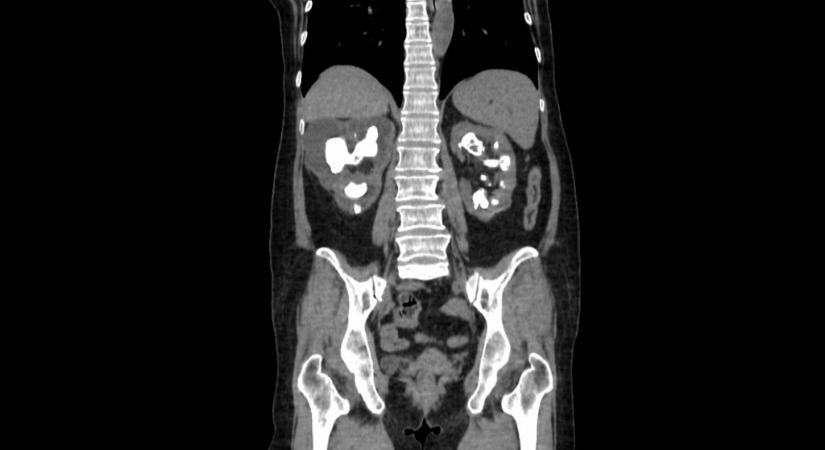

Egy új módszer mikroméretű robotokkal semmisíti meg a vesekövet

A robotok milliméter méretű, zselatin alapú polimercsíkokból készülnek és mágnesrendszer segítségével jutnak el a célpontig.